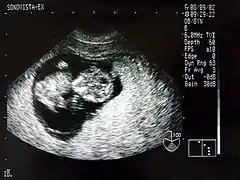

Échographie d'un fœtus de neuf semaines.

Dans le cadre de la surveillance médicale de la grossesse, une échographie permet d'obtenir une image monochrome d'un fœtus à l'intérieur du ventre de sa mère. Bien que ce soit l'utilisation la plus connue de l'échographie, on utilise également cette technologie pour la détection des troubles d'organes internes (calculs, kystes, cancers).